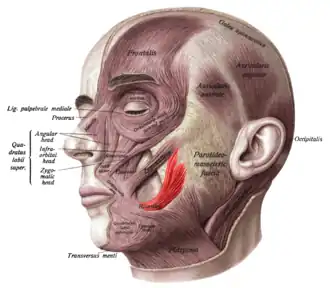

Superficial muscles of the head and neck, showing the risorius in red. This version of the muscle does not match that shown in most sources. | |